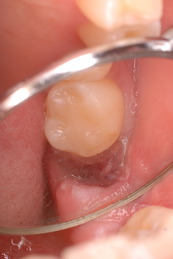

歯周病の疑いで東京のかなり遠方の方が来院されました。

驚くべきことですが、定期検診は受けていたそうです。しかしながら歯周病の指摘は受けたことがないそうです。

何故か?定期検診が虫歯のチェックのみになり、又肝心の歯周病の検査や歯周病の部分の予防や治療のためのブラシの使い方などを学んだ事がないのです。